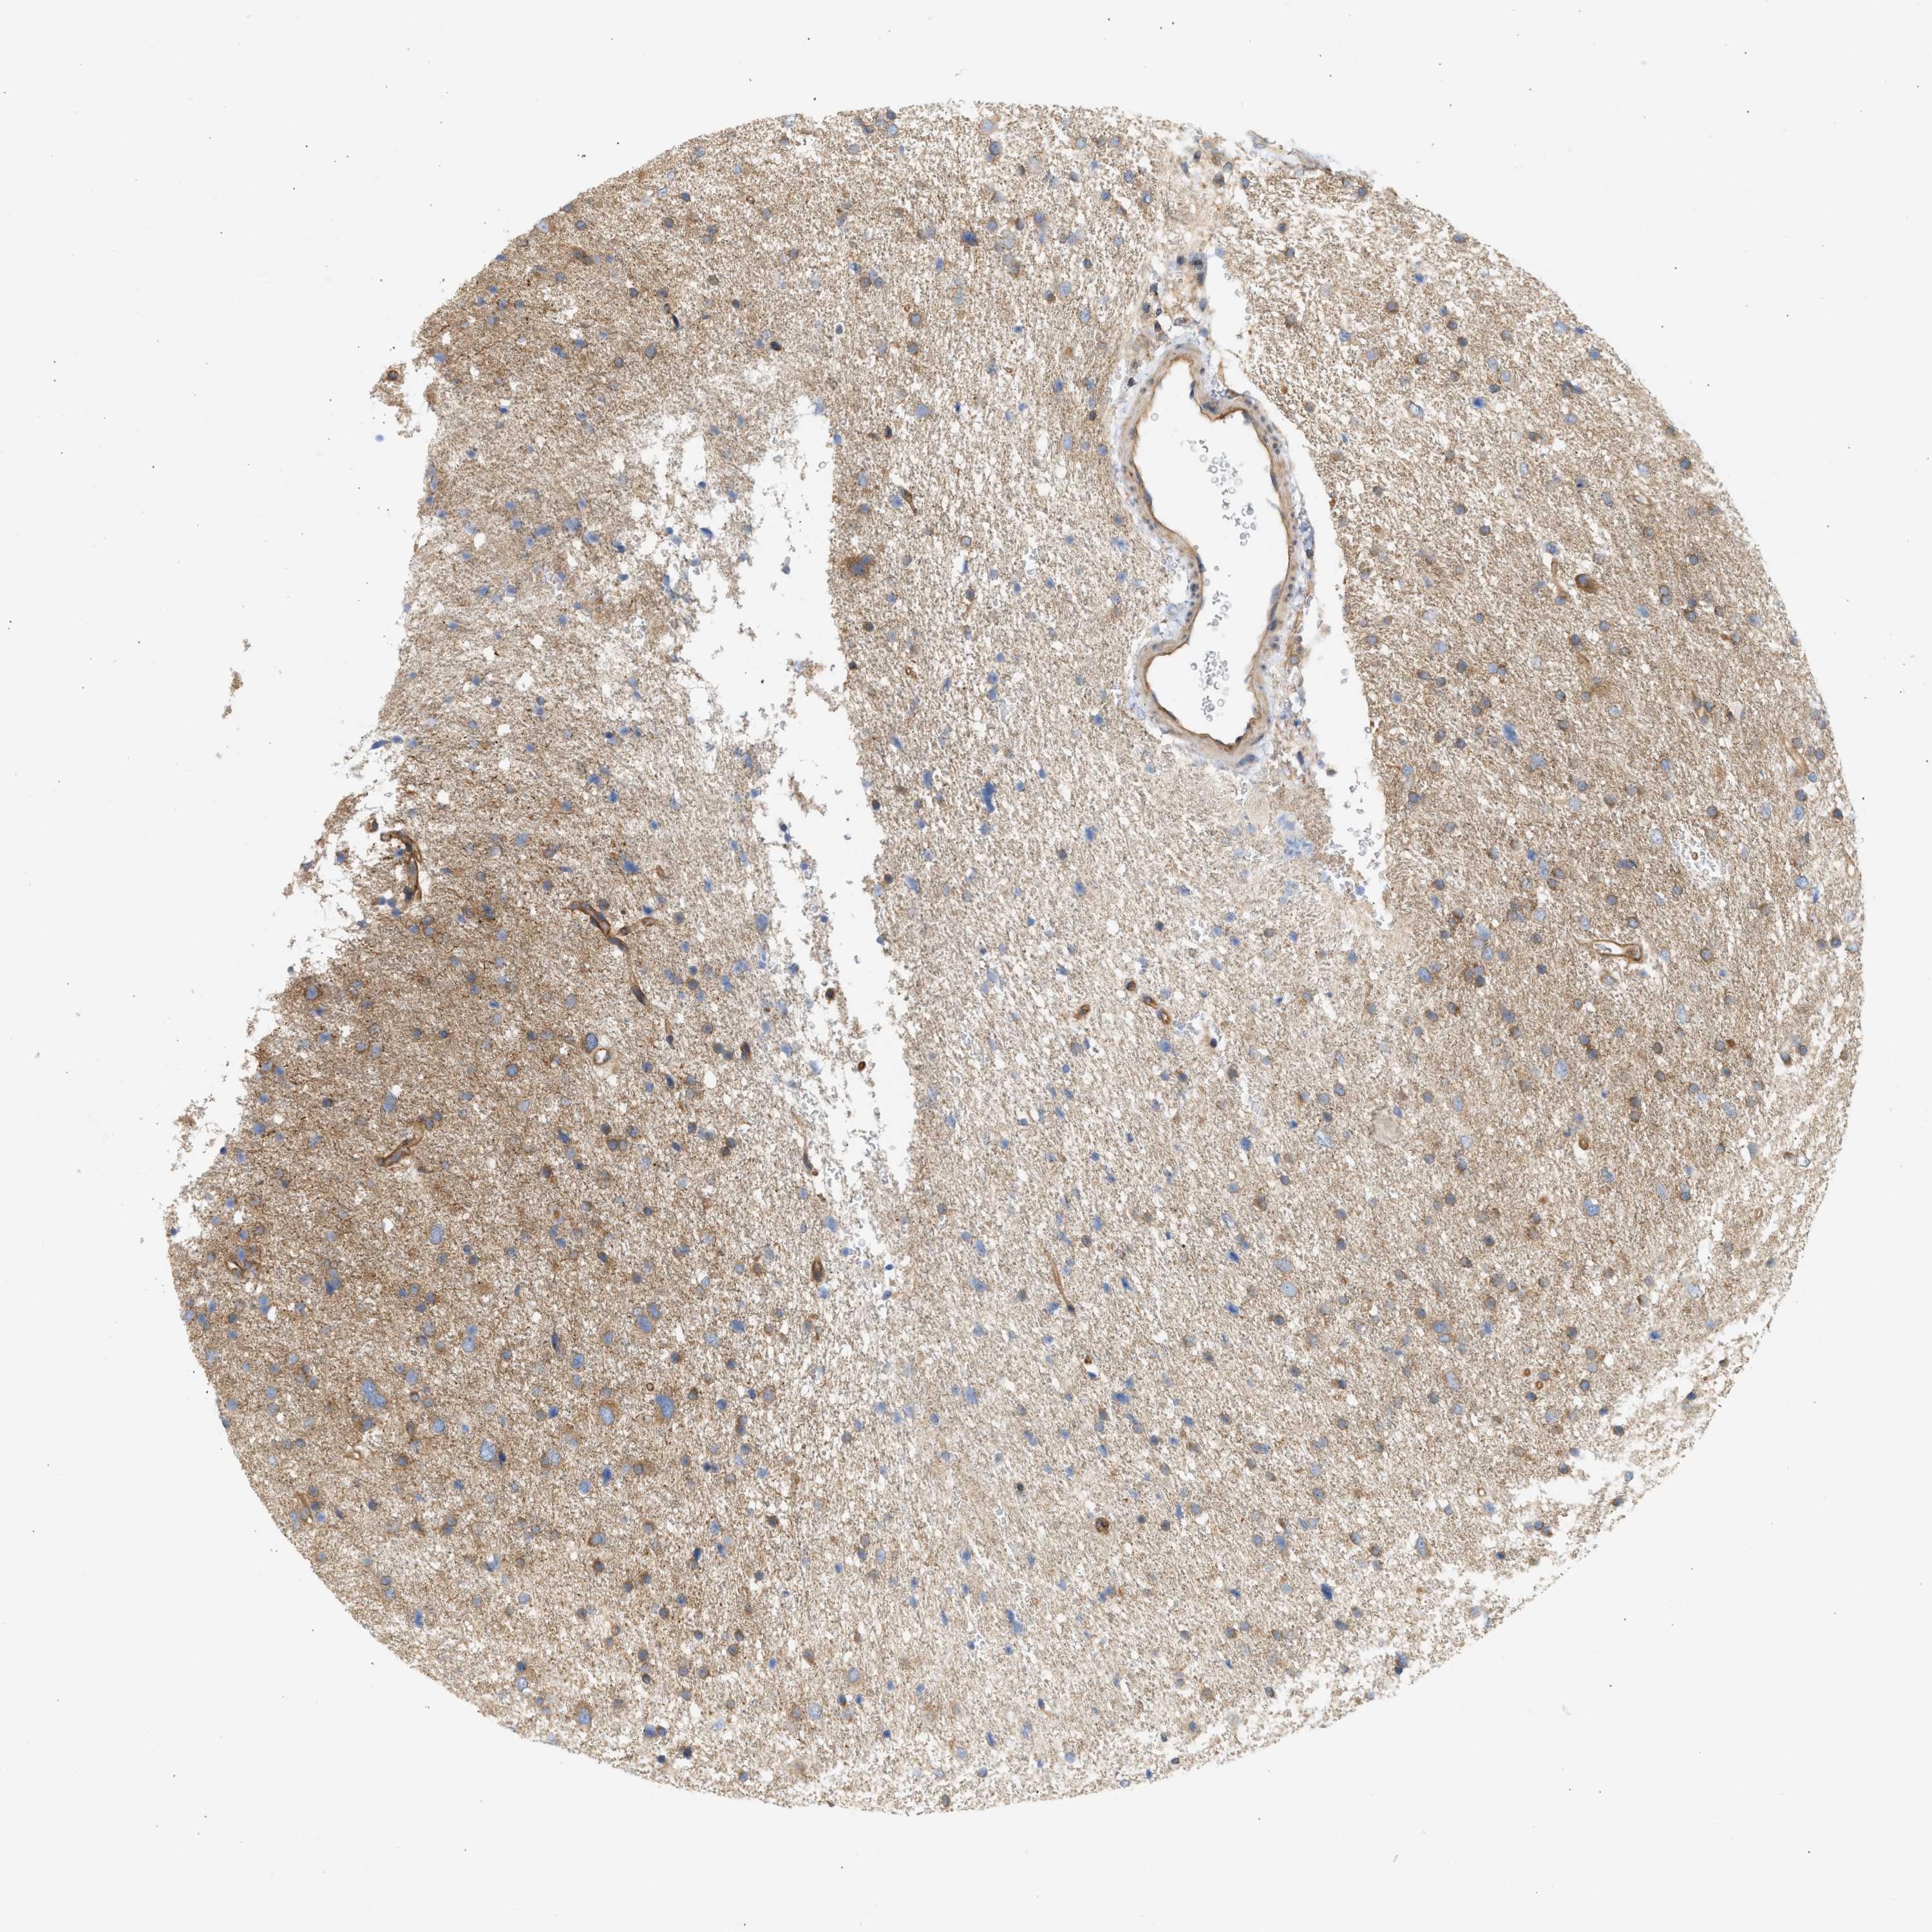

GLIOMA - Protein expressioni

A mouse-over function shows sample information and annotation data. Click on an image to view it in a full screen mode. Samples can be filtered based on level of antibody staining by selecting one or several of the following categories: high, medium, low and not detected. The assay and annotation is described here.

Note that samples used for immunohistochemistry by the Human Protein Atlas do not correspond to samples in the TCGA dataset.

Antibody stainingi

Antibody staining in the annotated cell types in the current human tissue is reported as not detected, low, medium, or high, based on conventional immunohistochemistry profiling in selected tissues. This score is based on the combination of the staining intensity and fraction of stained cells.

Each image is clickable and will lead to virtual microscopy that enables deeper exploration of all samples and also displays staining intensity scores, fraction scores and subcellular localization as well as patient and tissue information for each sample.

Antibody HPA017286

Staining

High

Medium

Low

Not detected

Intensity

Strong

Moderate

Weak

Negative

Quantity

>75%

75%-25%

<25%

None

Location

Nuclear

Cytoplasmic/membranous

Cytoplasmic/membranous,nuclear

Glioma, malignant, Low grade

Glioma, malignant, High grade